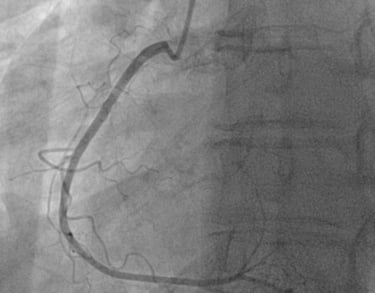

CORONAROGRAFIA

La Coronarografia è l’esame piu’ approfondito per valutare la presenza di restringimenti (“stenosi”) a carico delle arterie coronarie, ovvero delle arterie che nutrono il cuore. Viene effettuata tramite utilizzo di appositi cateteri che vengono inseriti attraverso l'arteria radiale o femorale. Per acquisire le immagini viene utilizzato un liquido chiamato “mezzo di contrasto” che opacizza il lume delle arterie mescolandosi al sangue. Le immagini vengono acquisite da un macchinario che emette una debole radiazione e registra le immagini.